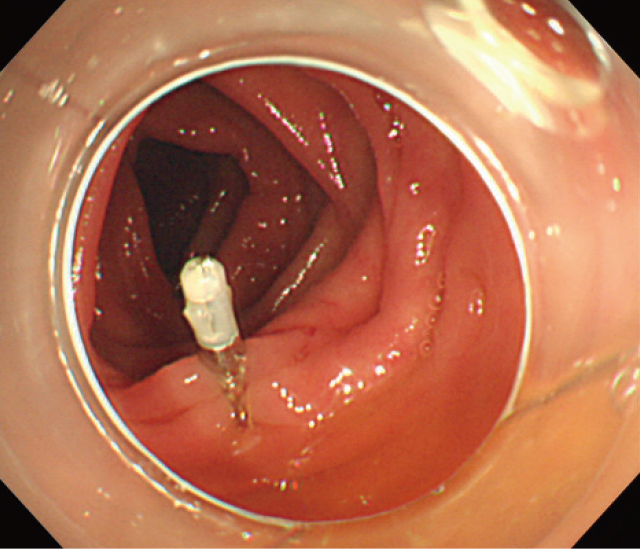

NonBleeding Visible Vessel(NBVV).

憩室内部をアタッチメントを装着したスコープで吸引し翻転させることでdome内の露出血管が確認された.